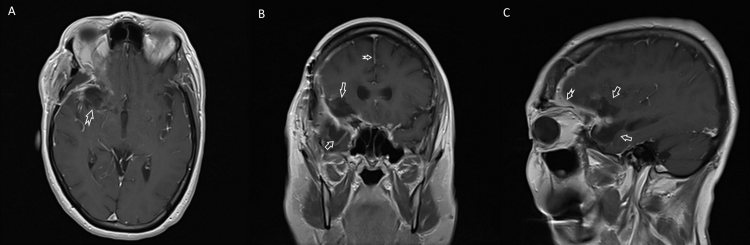

Fig. 4.

Postoperative gadolinium enhanced MRI images with (A) axial, (B) coronal, and (C) sagittal views. The surgical resection cavity with gross total resection is visible on (A) (notched arrow) and delineated by arrows in (B) and (C). The midline shift of the falx cerebri has resolved as illustrated by the notched arrow in (B), and there is dural enhancement visible in (C) (notched arrow) that represents normal postoperative effect.